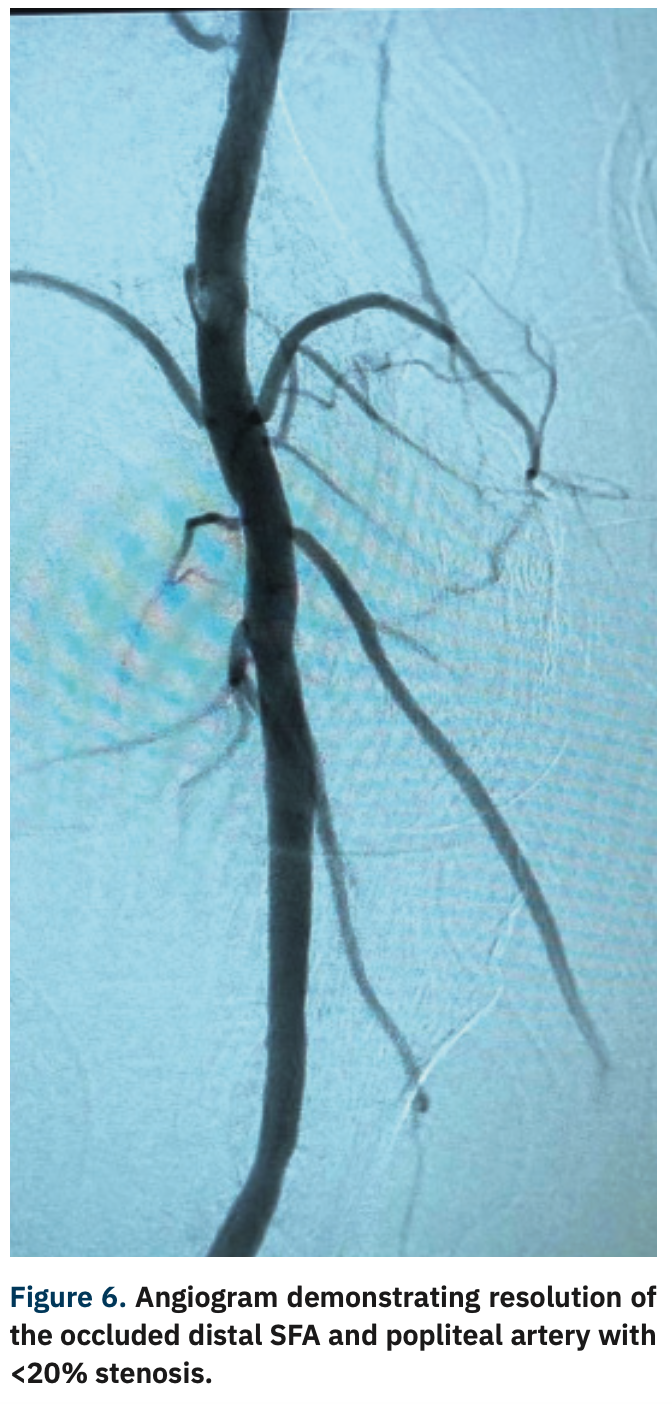

A complication occurred when removing the EPD filter when the tip broke into the popliteal artery, requiring removal (Figure 4). The Goose Neck loop snare (Medtronic) technique was used to effectively remove the two broken filter pieces (Figure 5). Following removal, final angiogram pictures were obtained, and demonstrated no dissection or perforation of the vessels (Figure 6). The distal SFA and popliteal artery occlusions resolved from 90% stenosis to <20% residual stenosis.